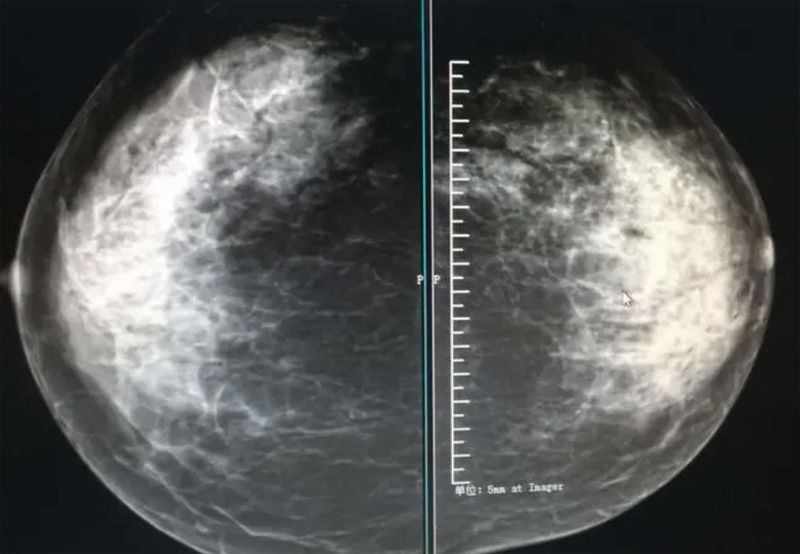

攝影診斷規(guī)范乳腺DR有頭尾位及內(nèi)外側(cè)斜位診斷概念和診斷術語

乳腺DR的檢查中為了讓乳腺相關疾病的篩查需要更高質(zhì)量的檢查圖像。檢查前期的準備工作非常重要。醫(yī)生跟病患的有效溝通。要跟檢查者說明檢查過程,特別是體位跟擠壓乳房帶來的不適應。放松心情,檢查過程中得到充分的合作。正確的擺正位置乳腺DR可以拍攝到更優(yōu)質(zhì)清洗高質(zhì)量的X線圖像。乳腺DR檢查需要再月經(jīng)后檢查,但是對病癥明顯的就不受這個限制。

乳腺DR攝影體位有頭尾位及內(nèi)外側(cè)斜位,

乳房在片子的中央,乳頭切線位,可見小部分胸大肌,內(nèi)側(cè)乳腺組織應全部包括在片中,外側(cè)乳腺組織盡可能包括在片中。一張好的MLO位圖像顯示如下:乳房被推向前上,乳腺實質(zhì)充分展開,胸大肌可見,較松弛,下緣達到乳頭水平,乳頭在切線位,部分腹壁包括在片中,但與下部乳腺分開,絕大部分乳腺實質(zhì)顯示在片中。乳腺組織外緣可見乳頭的輪廓;乳腺后方的脂肪組織被很好地顯示出來,乳房無皺褶。對于CC位及MLO位顯示不良或未包全的乳腺實質(zhì),可以根據(jù)病灶位置的不同選擇以下體位:外內(nèi)側(cè)位(LM)、內(nèi)外側(cè)位(ML)、內(nèi)側(cè)頭尾軸位(MCC)、外側(cè)頭尾軸位(LCC),尾葉位(CLEO)及乳溝位。在臨床實踐中,對于常規(guī)體位上發(fā)現(xiàn)的異常改變,可以進一步采取一些特殊的攝影技術,包括局部加壓攝影、放大攝影或局部加壓放大攝影技術。

3、乳腺實質(zhì)背景的確定:觀察乳腺實質(zhì)與脂肪的構成比例,了解乳腺實質(zhì)類型,以判斷對某些乳腺攝影征象敏感性的影響,有利于確定乳腺攝影對疾病的診斷價值。

必須指出的是,美國放射學會提出的乳腺影像報告和數(shù)據(jù)系統(tǒng)(Breast Imaging Reporting and Data System, BI-RADS)將乳腺分為4型:脂肪型(乳腺內(nèi)幾乎全部為脂肪組織,腺體組織占25%以下)、少量腺體型(乳腺內(nèi)散在腺體組織,大約占25%~50%)、多量腺體型(乳腺呈不均勻致密表現(xiàn),腺體組織大約占51%~75%)、致密型(乳腺組織非常致密,腺體組織占75%以上)。這種分型的主要意義在于說明X線對不同乳腺類型中病變檢出的敏感性不同,對發(fā)生在脂肪型乳腺中病變的檢出率很高,而對發(fā)生在致密型乳腺中病變的檢出率則有所降低,臨床醫(yī)師了解這一點很重要。